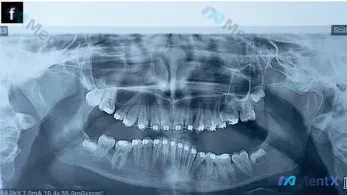

正畸治疗中的13岁全景片,除了阻生智齿还需关注什么?

整理了一份13.11岁患者的全景牙齿X光片资料,目前患者处于正畸治疗中,先放核心的影像学发现,大家看看第一眼的评估优先级会怎么排? 已知核心信息: - 恒牙列,全口可见正畸托槽与弓丝 - 双侧上颌第三磨牙已萌出,双侧下颌第三磨牙(38、48)呈近中阻生 - 下颌左侧第一磨牙(36)区域缺失 - 颌骨...